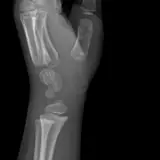

Over 2,100 interactive radiology cases, curated by radiologists for your level of training. Scroll, window, and view cases full screen — just like on PACS. Click linked findings in each writeup to jump straight to them on the image. Cases include sample reports, a focused discussion section, original illustrations, and videos.

Casos totalmente interactivos con las herramientas que esperaría de un PACS: scroll, ventana, zoom, pan, mediciones, ROI y modo de pantalla completa.

• Anotaciones enlazadas

Anotaciones extensas resaltan los hallazgos clave directamente sobre los casos. Haga clic en los hallazgos enlazados dentro de la descripción del caso para saltar a su ubicación exacta en el estudio.

Desplace, arrastre, ajuste ventana y amplíe como en una estación PACS de trabajo

Aprenda con eficiencia gracias a hallazgos de imagen anotados e ilustraciones